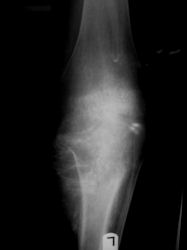

| Proximal Tibia Osteosarcoma: Limb-Sparing Surgery |

Intraoperative photos

Postoperative X-Rays

Examples of radical limb sparing surgeries for osteosarcomas in various anatomic locations (distal femur, proximal tibia, proximal humerus, scapula)

In each case, the tumor and bone from which it arose were resected. This required meticulous dissection, mobilization and preservation of adjacent pertinent neurovascular structures. In each case presented here, the defect was reconstructed with a special modular segmental tumor prosthesis. This also replaces the adjacent joint in many instances.